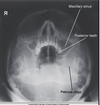

Q

what is the most lateral sinus when doing a waters

A

where are the petrous ridges on a waters

below maxillary sinuses/antrum

where is collimation on a waters sinus

edge of orbits

hairline to below open mouth